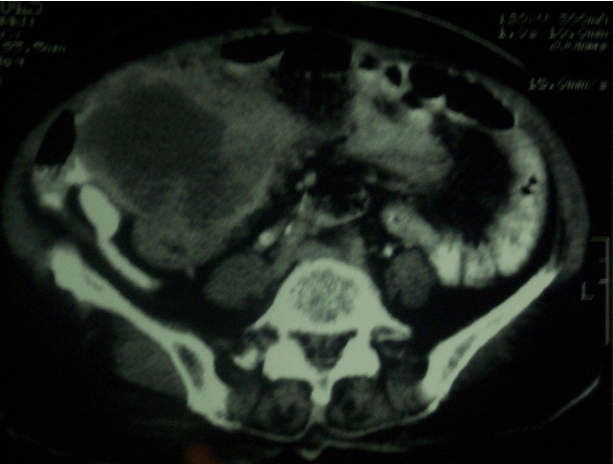

Computed tomography scan of the abdomen revealed (Figure 1) complex mass measuring 13x10x5 cm occupying the right upper quadrant which is inseparable from the gallbladder and the inferior liver margin. The transverse colon is displaced inferiorly. The rest of the organs appear to be normal. Impression is a gallbladder tumor possibly a sarcoma.

Cursor on image to zoom/Click text to open image

Figure 1: Preoperative computed tomography scan. Complex mass measuring 13x10x5 cm occupying the right upper quadrant which is inseparable from the gallbladder and the inferior liver margin.